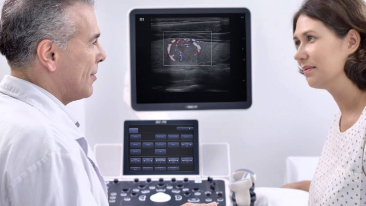

eXceeding Experience

YΟΦksek verimli deneyim

Tarama deneyiminin a??lmas?, hem netlik hem de kullan?m kolayl??? a??s?ndan, yΟΦksek kalitede muayene i?in daha fazla hasta oda?? sa?lar. X-Insight, beklentilerinizin ?tesinde daha iyi ergonomi, daha kolay tarama ve esnek y?netim sunarak, ola?anΟΦstΟΦ kullan?m kolayl??? sa?lar.

Net ve Ayr?nt?l? - Full HD Etkile?im

? 21,5 in?/23,8 in? Full HD Monit?r

? A?? Ayarl? 13,3 in? Ultra ?nce Dokunmatik ekran